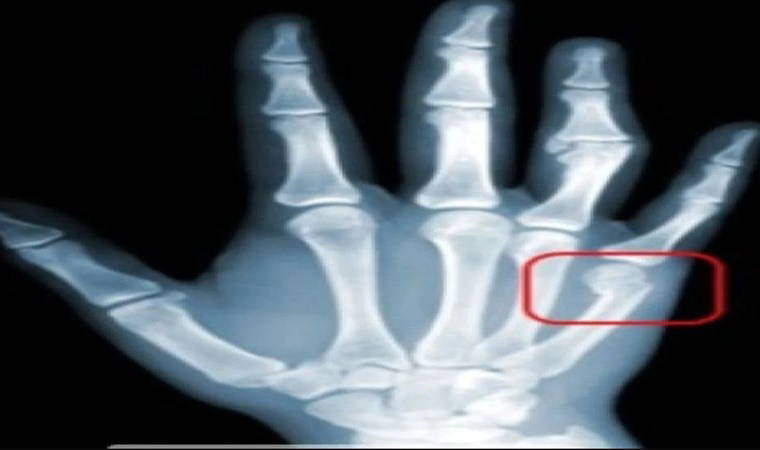

'Smartphone pinky' akıllı telefonların aşırı kullanımına bağlı olarak gelişen yeni bir rahatsızlık. Uzun süreli kullanımlarda serçe parmaklarında belirgin bir çöküklük olduğunu fark edenlerin yanı sıra şekil bozukluğu ile kalmayıp ilerleyen süreçte ağrı ve şişlik sorunuyla karşı karşıya kalanlar da var.

Sputnik'te yer alan habere göre bunun nedeni, uzun süreli cep telefonu kullanımı elde deformasyona neden olması, bu deformasyonun da bölgedeki tendonların ödemlenip deforme olmasına ve kronik ağrıya yol açması olarak açıklanıyor.

Akıllı telefon kullananların genellikle serçe parmaklarında değişiklikler gözlemlenirken, daha küçük bir telefon veya dokunmatik ekran yerine tuşlu telefonlar kullananlarda ise aynı semptomlar başparmakta görülüyor.

Günün her saatinde ve her mekanda akıllı telefonların sürekli elde ve sürekli parmakların kullanıldığını belirten Prof. Dr. Ersözlü, “Mesajlaşma başta olmak üzere aşırı kullanıma bağlı el ve başparmak sorunları özellikle genç yaştaki kişileri etkilemektedir. Parmakları hareket ettiren tendonların aşırı kullanımına bağlı zorlanmaları tendonlarda kalınlaşmalara (nodülleşme) sebep olarak hareketler sırasında takılmaya ve ağrıya yol açmaktadır. Tetik parmak olarak isimlendirdiğimiz bu durumun en önemli sebebi parmağın aşırı kullanılmasına bağlı tekrarlayan, zorlayıcı hareketler ve parmağa aşırı güç uygulanmasıdır. Telefon kullanımında en fazla başparmak zorlanmakta buna bağlı tetik parmakta en fazla başparmakta görülmektedir. Tetik parmak oluşumunda ilk belirti parmakta ağrıdır. İlerlediği zaman olaya parmakta takılma ve kilitlenme de eşlik eder. Bu nedenle parmak ağrısı ciddiye alınmalıdır. Erken tanı ile tedavi edilebilecek olan bu durum ihmal edildiğinde cerrahi müdahale gerektirecek bir sorun haline dönüşebilir. El bileği ve başparmağın aşırı kullanımına bağlı zorlanması ile De-Quervain Hhiği zaman cerrahi müdahale ile tedavi edilebilen bir tendon sıkışmasıdır” şeklinde konuştu.